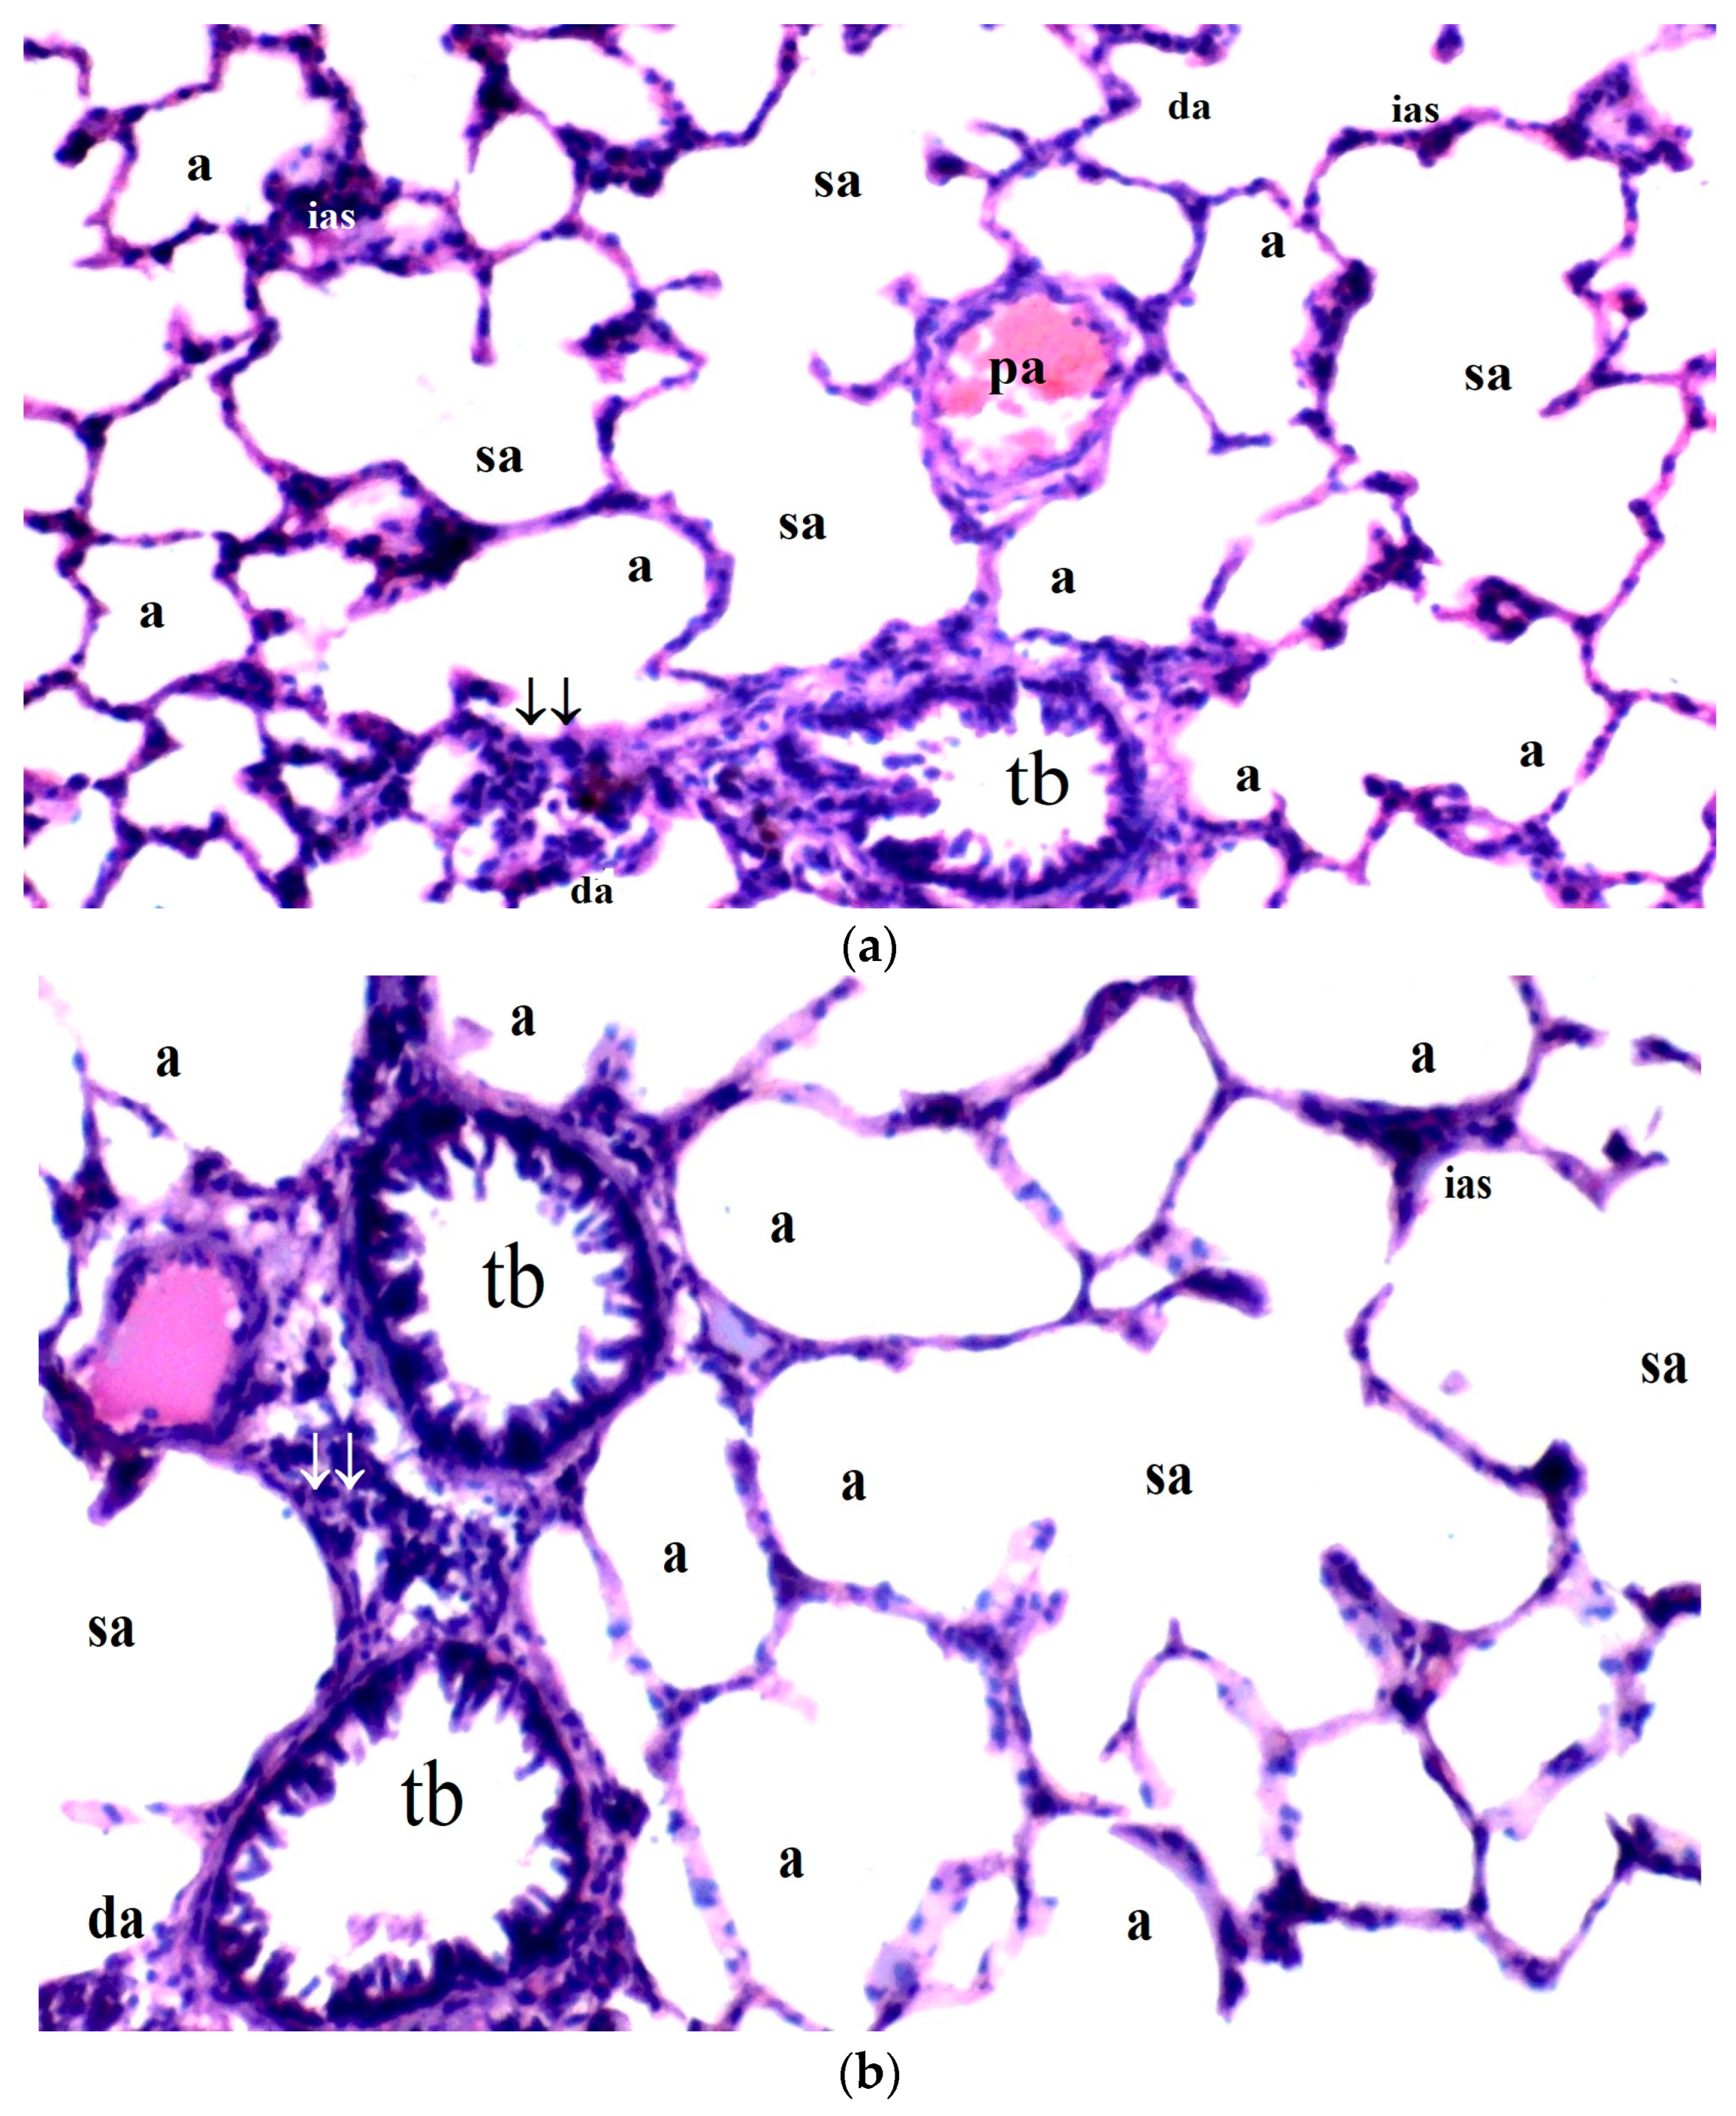

3.2.2. Lung Tissue

Significant differences were observed among the groups regarding interstitial edema in lung tissue (p = 0.027). Interstitial edema was more prominent in the IR group compared to the control and BPC groups (p = 0.009 for both). However, interstitial edema was significantly reduced in the IR-BPC group compared to the IR group (p = 0.032) (Table 5, Figure 2).

Figure 2.

(a–d) Histopathological examination of lung tissues of C, B, IR and IR-BPC groups. (a): Normal lung tissue in group C, (b): lung tissue of group B, (c): lung tissue of group IR with increased leukocyte infiltration and thicker of the alveolar walls, (d): lung tissue of group IR-BPC with mild degeneration compared to group IR. Abbreviations: a—alveolus, sa—saccus alveolaris, da—ductus alveolaris, conj—congestion, tb—terminal bronchiole, ias—interalveolar septum, pa—pulmonary artery, ↓↓—parenchyma, rb—respiratory bronchiole, cong—capillary congestion.

Alveolar congestion also exhibited significant differences between the groups (p = 0.019). The IR group demonstrated a higher degree of alveolar congestion compared to the control and BPC groups (p = 0.004 and p = 0.012, respectively). In the IR-BPC group, alveolar congestion was significantly lower than in the IR group (p = 0.040) (Table 5, Figure 2).

Leukocyte infiltration (neutrophil/lymphocyte) was significantly different among the groups (p = 0.008). Leukocyte infiltration was more frequent in the IR group compared to the control and BPC groups (p = 0.002 and p = 0.006, respectively) (Table 5, Figure 2).

The thickness of the alveolar walls also differed significantly between the groups (p = 0.008). The IR group had significantly thicker alveolar walls compared to the control and BPC groups (p = 0.002 and p = 0.006, respectively) (Table 5, Figure 2).

In terms of the total damage score, significant differences were observed among the groups (p = 0.004). The total damage score was higher in the IR group compared to the control and BPC groups (p = 0.001 and p = 0.002, respectively). However, the total damage score was significantly reduced in the IR-BPC group compared to the IR group (p = 0.042) (Table 5, Figure 2).